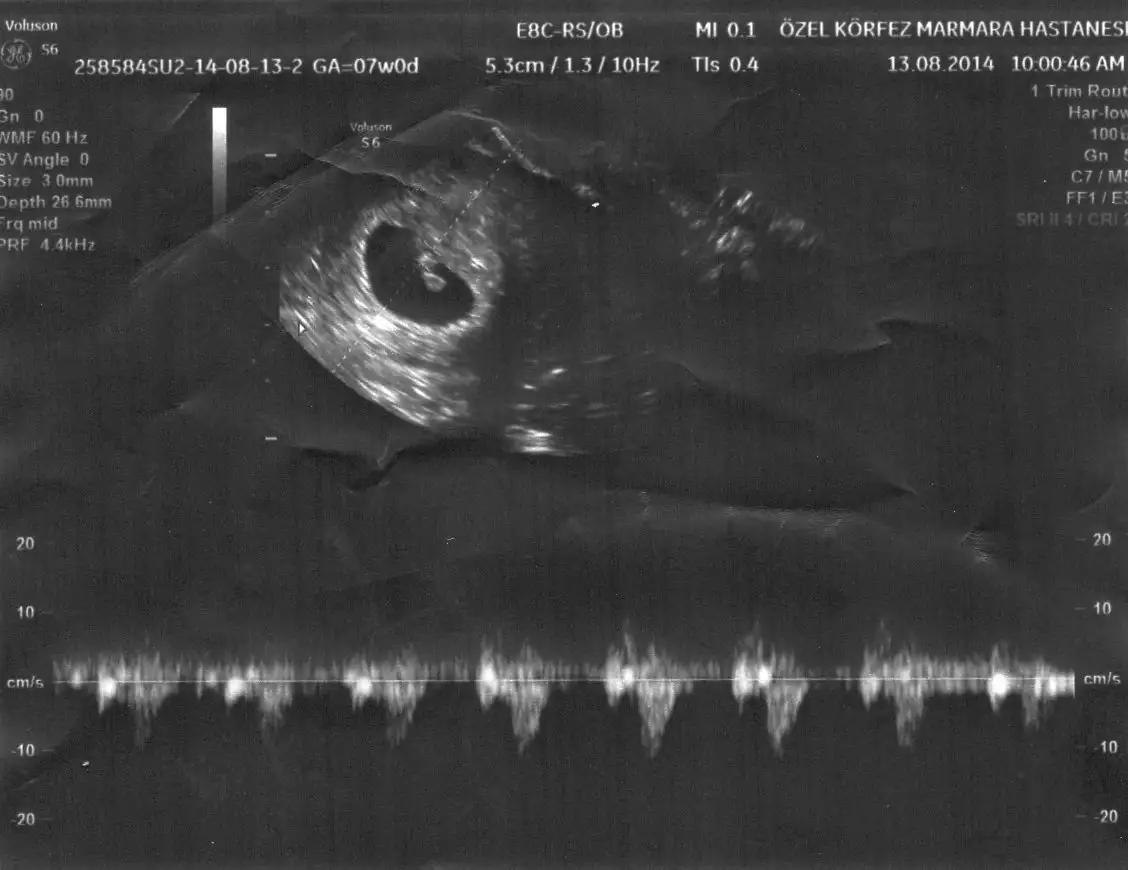

Maşallah senin bebişin aynen fasulye gibi çıkmış kız mı acaba gönlünden geçen ne bilmem ama bana öyle geldiTeyzeleri bu da benim miniğim burda 7+0 dık sizde atın sizin miniklerinizi görelim Burda pıt pıtlarını duymuştuk :) Maaşallah demeyi unutmayın

maşallah Rabbim nazarlardan saklasin bugün bizde doktora gidiyoruz inş meleğini gorucem bugünTeyzeleri bu da benim miniğim burda 7+0 dık sizde atın sizin miniklerinizi görelim Burda pıt pıtlarını duymuştuk :) Maaşallah demeyi unutmayın

Maşallah kuzuya maşallah nazar değmesin ben de bu hafta duyucam Allah nasip ederse :)Teyzeleri bu da benim miniğim burda 7+0 dık sizde atın sizin miniklerinizi görelim Burda pıt pıtlarını duymuştuk :) Maaşallah demeyi unutmayın